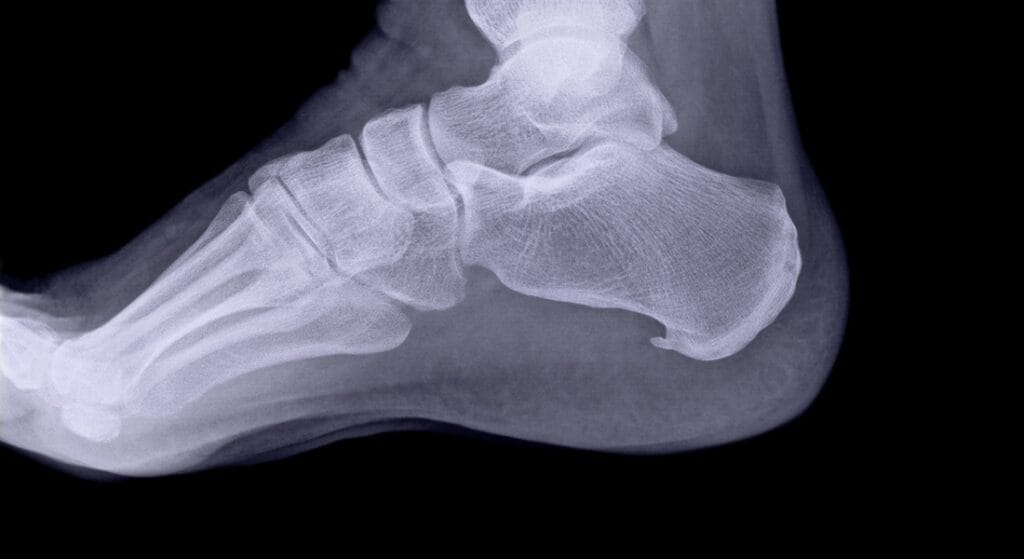

- X-quang: phát hiện gai gót, thoái hóa khớp, gãy xương vi chấn thương